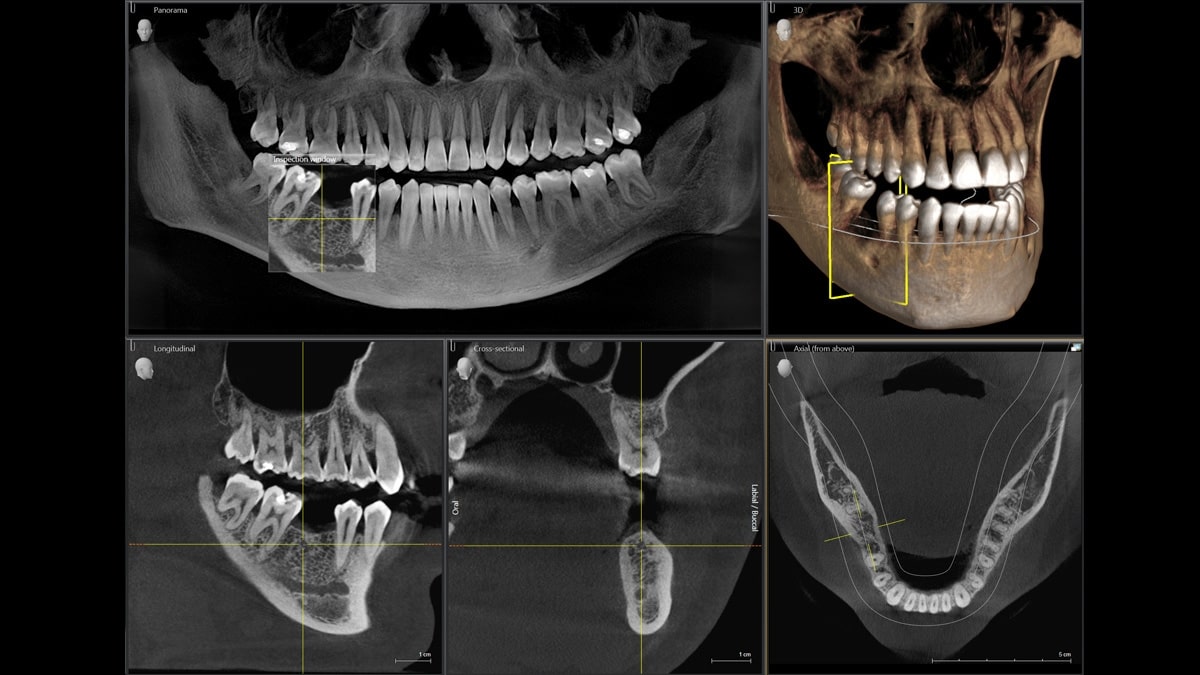

Новые технологии: 3D-рентген

Новозеландская компания MARS Bioimaging совместно с научно-исследовательскими институтами Отаго и Кентербери предложила новую уникальную разработку — рентген-оборудование, предоставляющее цветные трехмерные изображения.

Стандартная техника работает по привычному нам алгоритму: получению двумерных, “плоских” снимков. Достоверную и полную информацию о состоянии органа можно “считать” при объемной картинке, поэтому снимки во время рентгенографии приходится делать в нескольких проекциях.

Рентгеновские лучи проходят через структуры тела по-разному: чем тверже ткани, тем лучше их поглощают и, соответственно, четче и светлее отражаются на пленке или цифровых экранах. Мягкие или жидкие структуры на изображениях имеют серый или темный оттенок. Таким образом, принцип работы рентгенологического аппарата: лучи встречают препятствия на своем пути (интенсивность их поглощения зависит от плотности тканей) и формируют картинку.

Оборудование, предложенное новозеландскими исследованиями, работает немного иначе: оно учитывает не только момент проникновения лучей в ткани организма, но и малейшие изменения электромагнитных волн во время их “путешествия” . То есть фиксирует любую разницу внутренних структур, пока проходит до и сквозь них. Сигналы обрабатываются техникой, позволяя получить объемные снимки органов. Это ноу-хау превращает рентген в эффективный исследовательский инструмент, не уступающий современным дорогостоящим томографам. 3D-рентген — пока еще новое направление медицине, активно набирающее обороты. Но за этими установками будущее, позволяющее проводить точные, быстрые, безопасные исследования и спасать миллионы жизней людей на планете.